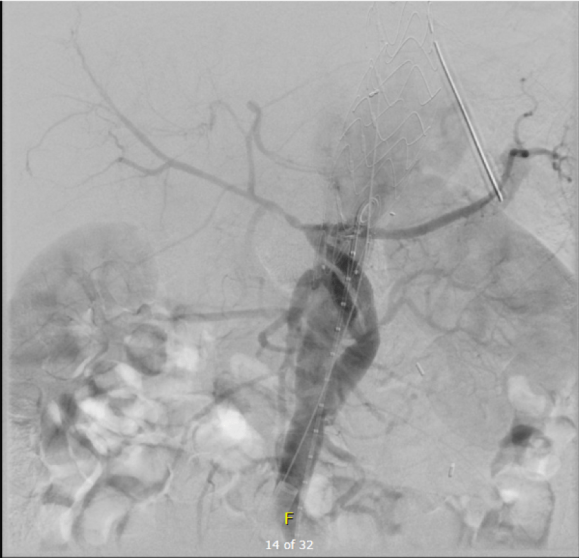

As seen below, the graft excluded the celiac and SMA. Late in the phase of the final aortogram (second panel) there was an endoleak that persisteed despite multiple ballooning. The timing suggested the intercostals and phrenic vessels contributed to a type II endoleak, but it was concerning.

This worked to relieve the kink as evidenced on the aortogram above. After closing the laparotomy, I placed a chest tube in the right chest. The patient had a course prolonged by a classic systemic inflammatory response syndrome, with fevers, chills, and leukocytosis. He bled for a while but stopped with correction of his coagulopathy. All blood cultures were negative, but a CT scan was performed out of concern for the endoleak, and the possibility of continued bleeding.